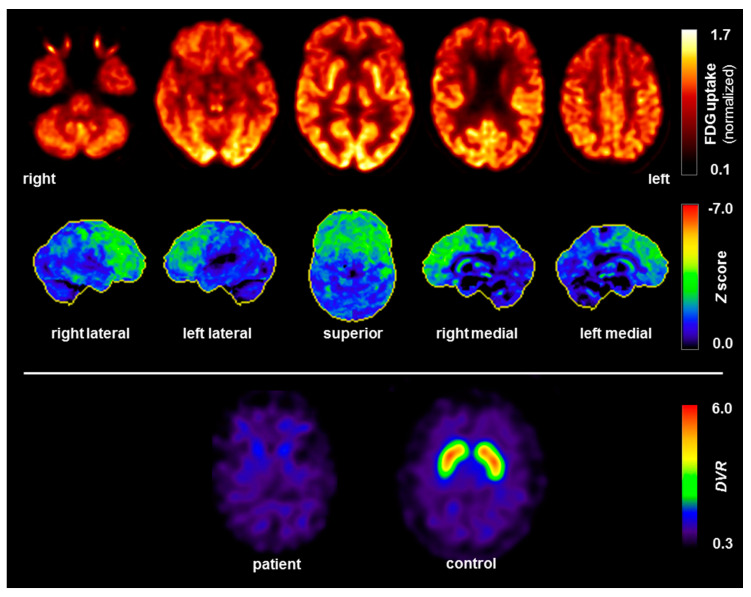

Following admission to our specialized ward at the age of 63, three years after the onset of the neuropsychiatric syndrome, a comprehensive clinical examination was performed. The MRI of the brain revealed low-grade mesencephalon atrophy, but there was no clear “hummingbird sign”. Other brain regions, including the basal ganglia and limbic system, were unremarkable (Figure 2). The MRI of the spinal cord showed no evidence of myelopathy or contrast-enhancing lesions. In the visual assessment and independent component analyses, the EEG was normal. The CSF revealed slightly increased protein concentration. The anti-GlyR serum IgG antibody titers were 1:80 (reference: <1:20; Laboratory Krone, Bad-Salzuflen, Germany), and the CSF testing was negative (identical OCBs in serum and CSF were no longer positive). Tau, p-tau and β-amyloid quotients were in the normal range. In addition, slightly elevated anti-thyroid peroxidase (TPO) antibodies were found in the serum (Table 1). The FDG PET depicted a moderate bilateral hypometabolism of the frontal lobes, the midbrain, and, to a lesser extent, the caudate nuclei as well, compatible with a frontotemporal lobar degeneration (Figure 3). On the whole body FDG PET/CT, there was no indication of a neoplastic process. For examination of nigrostriatal degeneration, which in severe expression would be more typical for PSP than FTD, an FPCIT SPECT was performed, which revealed a severely reduced dopamine transporter availability in both striates, indicating pronounced nigrostriatal degeneration (Figure 3). Thus, nuclear medicine findings are well compatible with PSP [ref. 5,ref. 6,ref. 11], whereas the lack of asymmetry argues against CBD [ref. 6,ref. 10,ref. 11]. In the neuropsychological testing of attention performance (TAP), a clear impairment of both basal and more complex attention functions was detected. The “Consortium to Establish a Registry for Alzheimer’s Disease” (CERAD) test battery revealed deficits in verbal memory and executive performance (word fluency, set-shifting; Figure 4).

In the absence of oculomotor abnormalities, the presence of a frontal syndrome and mild postural instability leads diagnosis towards a “suggestive frontal PSP” [ref. 5]. The (only) minimal improvement with levodopa and the tendency to fall would also be compatible with PSP [ref. 3]. A supranuclear palsy of the eye was not currently present, but this symptom can occur after a delay [ref. 2]. Alternatively, the clinical diagnosis could be probable CBD, with frontal behavioral-spatial syndrome and asymmetrical Parkinsonism [ref. 7]. The nuclear medicine findings, which showed hypometabolism of the frontal lobes, midbrain and caudate nucleus on FDG PET, as well as strongly reduced dopamine transporter availability in both striates on FPCIT SPECT, are well in line with PSP [ref. 5,ref. 6], whereas the lack of asymmetry in both examinations argues against CBD [ref. 6,ref. 10,ref. 11]. There was a low-grade midbrain atrophy, which did not decisively argue for or against one of the two 4-repeat tauopathies [ref. 5,ref. 25,ref. 26]. In summary, the patient appeared to be suffering from a Parkinsonian syndrome with prominent frontal lobe involvement, but a definitive PSP or CBD diagnosis could not be made. This is in line with the notion that the 4-repeat tauopathies PSP and CBD may be considered to represent different manifestations of a disease spectrum with several common clinical, neuroimaging, pathological, genetic and biochemical features, which prohibits accurate in vivo distinction between both diseases [ref. 11,ref. 27].